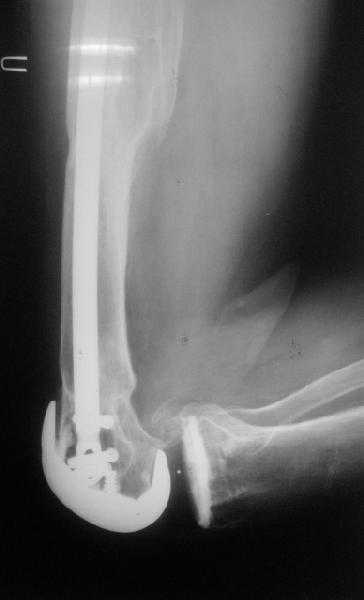

Видимо, самое "модное" на сегодня - малоинвазивный остеосинтез пластиной с угловой стабильностью. Распространенный вариант и закрытый интромедуллярный остеосинтез ретроградно. Хотя у нас было бы сделано антеградно - лешево и сердито, действительно малоинвазивно, в сустав не надо влезать. Нет риска прорезания порозной кости с миграцией в сустав, что возможно при ретроградном - гвоздь вводится через вырез в бедреннм компоненте, туда же может и вывалиться. А антеградный - упрется в протез. Как раз вчера заходил больной через полтора года после такой операции. Снимки в приложении.

Абсолютно согласен с А.Челноковым, есть определённый опыт применения пластин с угловой стабильностью. Здесь очень хорошо подойдёт LCP DF, она хорошо адаптироваана по мыщелкам, а открытым способом вообще

прекрасно получится. В области дистального фрагмента можно провести до 6 винтов в конвергенции поэтому можно получить абсолютную стабильность, несмотря на короткий отломок.